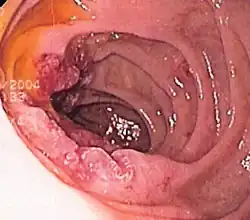

Endoscopic still of esophageal ulcers seen after banding of esophageal varices, at time of esophagogastroduodenoscopy